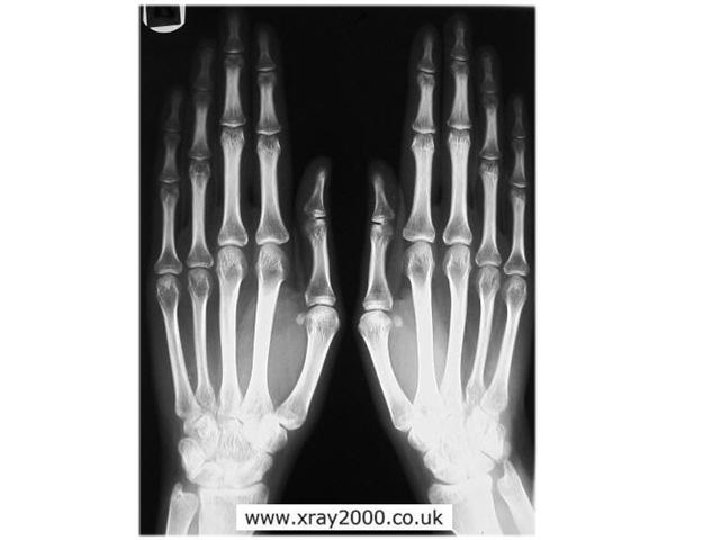

Joints A joint, or articulation, is the place where two bones come together. • Fibrous- Immovable: connect bones, no movement. (skull and pelvis). • Cartilaginous- slightly movable, bones are attached by cartilage, a little movement (spine or ribs). • Synovial- freely movable, much more movement than cartilaginous joints. Cavities between bones are filled with synovial fluid. This fluid helps lubricate and protect the bones.

Types of Synovial Joints Based on Shape Figure 5. 29 a–c Copyright © 2003 Pearson Education, Inc. publishing as Benjamin Cummings Slide

Types of Synovial Joints Based on Shape Figure 5. 29 d–f Copyright © 2003 Pearson Education, Inc. publishing as Benjamin Cummings Slide

Gliding- In a gliding or plane joint bones slide past each other. Mid-carpal and midtarsal joints are gliding joints. (Hands, Feet)